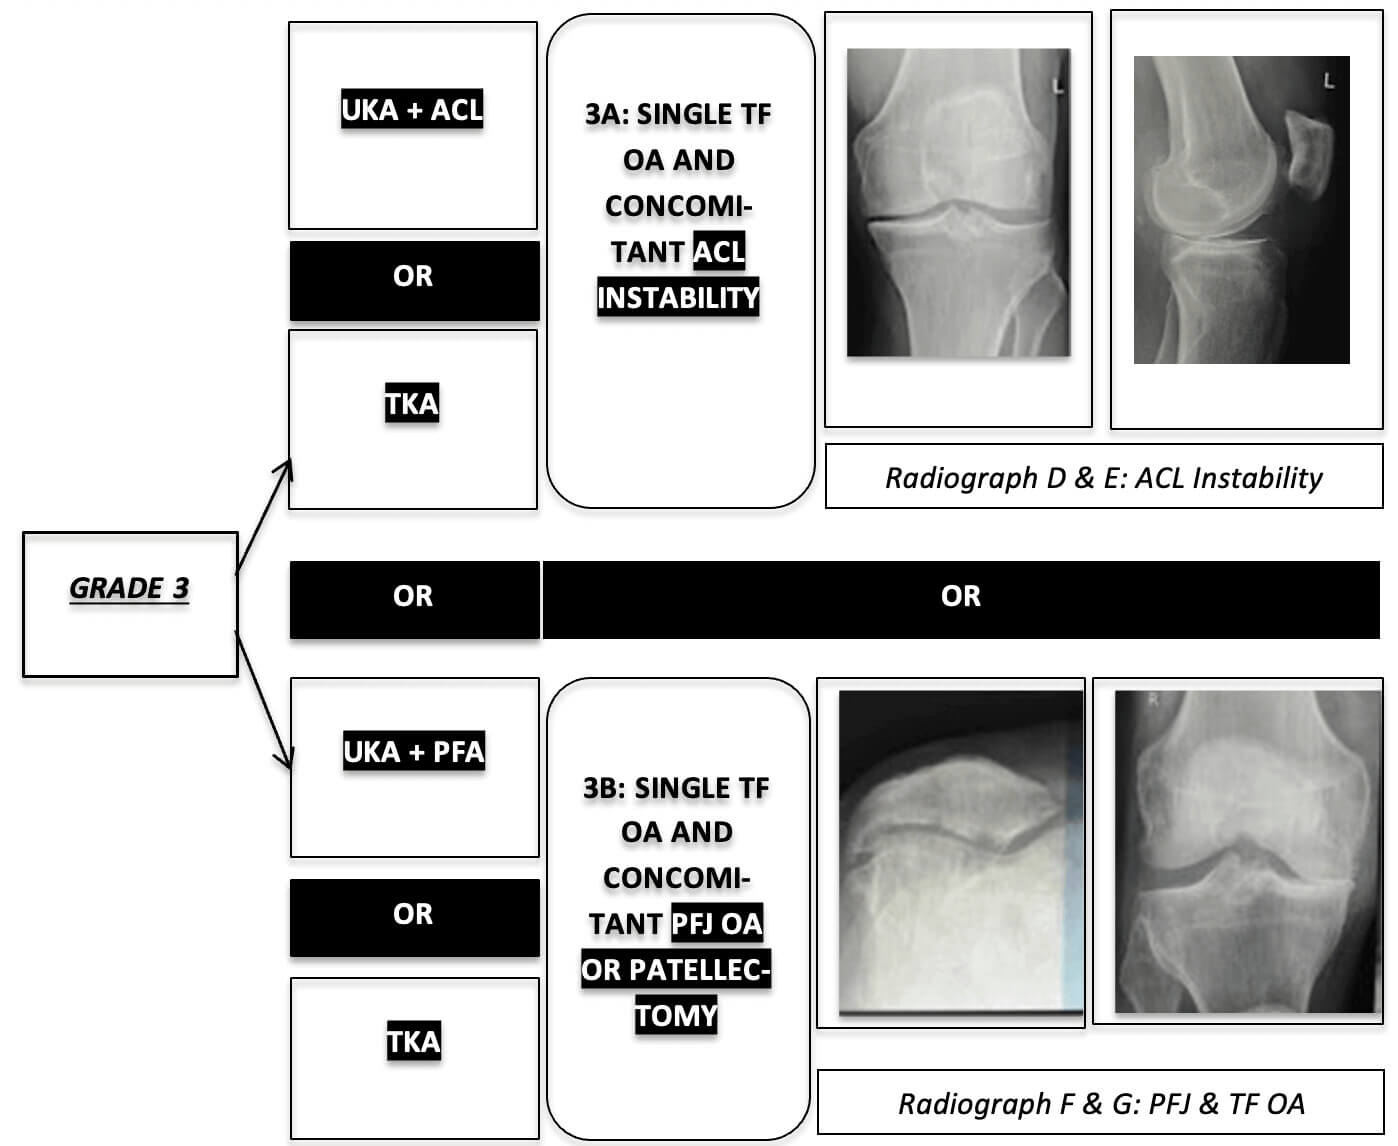

Footnote: Osteophytes are not a Contra-Indication. Confirm Contra-Lateral TF Space is > 5mm. Stress Reduction of Subluxation. No “Wedge Sign” (JLCA Less than 2 Degrees)